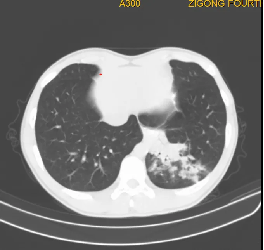

3. 胸部CT表现:

1)支气管壁增厚:这是支原体肺炎的一个常见CT表现,表现为沿支气管分布的增厚。

2)树芽征:这是由于细支气管和肺泡的炎症导致的,表现为CT影像上的细小、分支状的阴影。

3)磨玻璃影;

4)斑片状、节段乃至大叶性实变;

5)小叶中心结节:;

6)背景磨玻璃(树雾征);

8)胸腔积液;

9)少见影像征象。